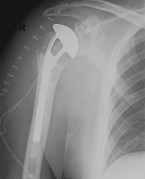

Abbildung9Abbildung10 Special prostheses such as an inverse shoulder prosthesis (syn.: "Delta prosthesis", "Grammont prosthesis") for the combination of severe omarthrosis with joint instability and rotator cuff defects

Right: radiograph of an inverse shoulder prosthesis for rotator cuff defect arthropathy.

left: Inverted shoulder prosthesis (Aequalis reversed type, Tornier company).